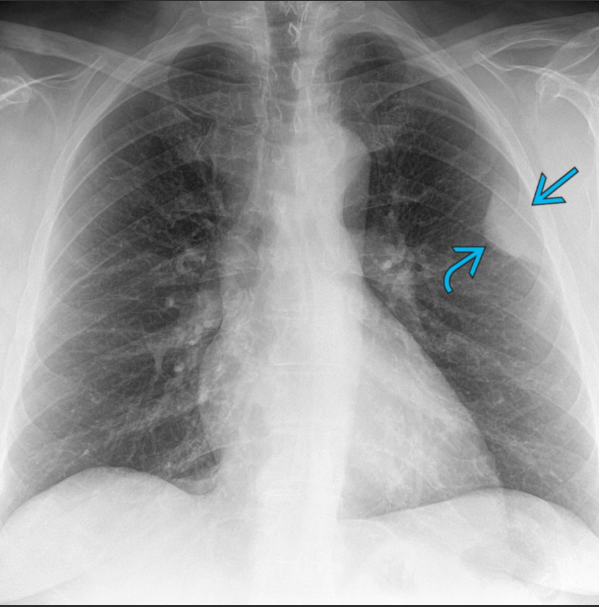

Provavelmente lesão intrapulmonar ou extrapulmonar?

Massa periférica alongada de partes moles no hemitórax esquerdo.

A lesão apresenta o sinal da borda incompleta, caracterizado por:

Borda medial nitidamente delimitada (seta curva em ciano);

Borda lateral mal definida (seta reta em ciano);

Achado compatível com localização extrapulmonar (pleural) da lesão.